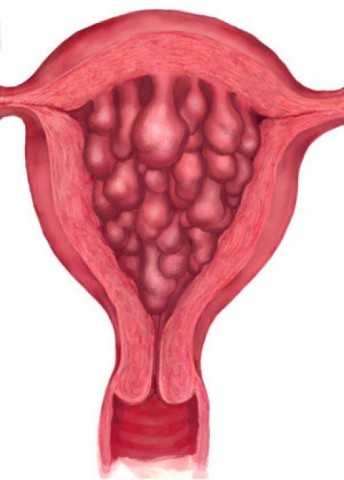

Медицинская диагностика: Гиперплазия эндометрия на УЗИ